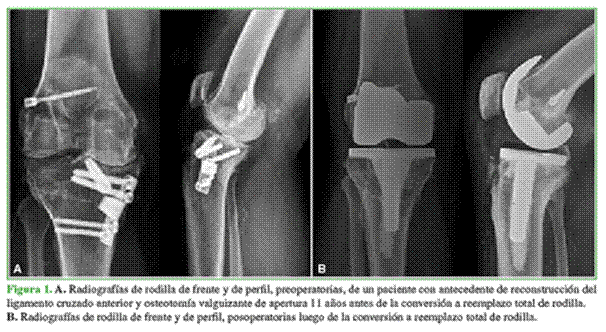

Con respecto al abordaje, en rodillas con OTA de apertura, fue pararrotuliano medial, a través del cual se retiró el material de osteosíntesis, ya que se obtuvo un acceso directo, y se realizó la artroplastia (Figura 1); en cambio, en la OTA de cierre que presentaban placa y tornillos, se realizaron dos abordajes independientes: uno sobre la cicatriz lateral para retirar la osteosíntesis y otro longitudinal anterior a través del cual se realizó el RTR, siempre dejando un espacio mínimo de 5 cm entre ambas incisiones. Como alternativa, en tres pacientes, se decidió retirar solo los tornillos proximales de la osteosíntesis a través de incisiones pequeñas para liberar el segmento proximal de la tibia y colocar el componente tibial dejando la osteosíntesis in situ (Figura 2).

Se utilizaron vástagos tibiales en siete casos con la finalidad de sobrepasar la zona de debilidad generada por la OTA (Figura 3). Además, se colocó un vástago en un paciente con retraso de la consolidación en el sitio de la OTA y en otro con un valgo severo de 25° en el que se utilizó una prótesis constreñida.

En dos oportunidades, se colocaron vástagos con offset debido a la traslación lateral de la epífisis tibial y la medialización del canal medular.